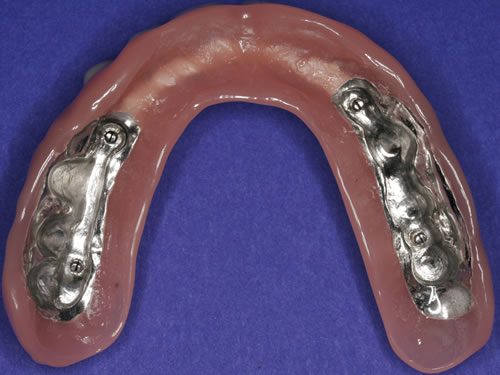

Für den zahnlosen Ober- und Unterkiefer werden dies häufiger Stegkonstruktionen oder Teleskopversorgungen sein (Abb. 8.8 bis 8.16).

Abb. 8.8: Individueller Steg auf 4 Implantaten im zahnlosen Unterkiefer.

Abb. 8.9: Eingesetzter prothesenartiger Zahnersatz.

Abb. 8.10: Individueller Stahlsteg auf 4 Implantaten im zahnlosen Oberkiefer.

Abb. 8.11: Eingegliederter graziler, herausnehmbarer, gaumenfreien Zahnersatz.